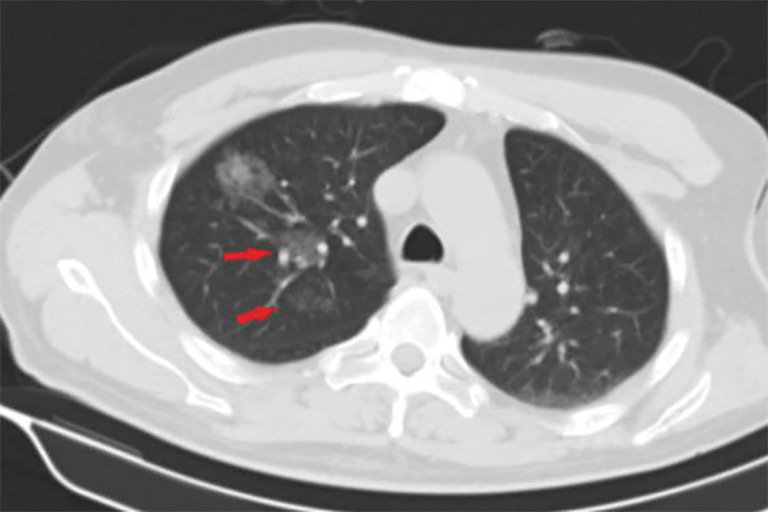

Figure 3.

Computed tomography (CT) image of small pulmonary nodules in the right upper lung lobe of a 48-year-old male. After injection of the suspension of surgical glue and methylene blue, diffusion of methylene blue into lung tissues is observed (red arrow).

Previously published studies have reported that the diffusion of methylene blue in the lung parenchyma makes it difficult to determine the location of SPNs, and their relationship with surrounding structures. They recommend that VATS should be performed within 3h following methylene blue injection (17,18). In the present study, methylene blue was used together with surgical glue to avoid diffusion; however, diffusion was still observed in 2 patients during VATS (Figure 3). Although surgery and pathological diagnoses were not affected, it is still recommended that the 2 fluids are completely mixed and that VATS is performed without delay. In the pulmonary nodule localization needle group, SPNs were localized accurately, and neither displacement nor dislocation was observed.